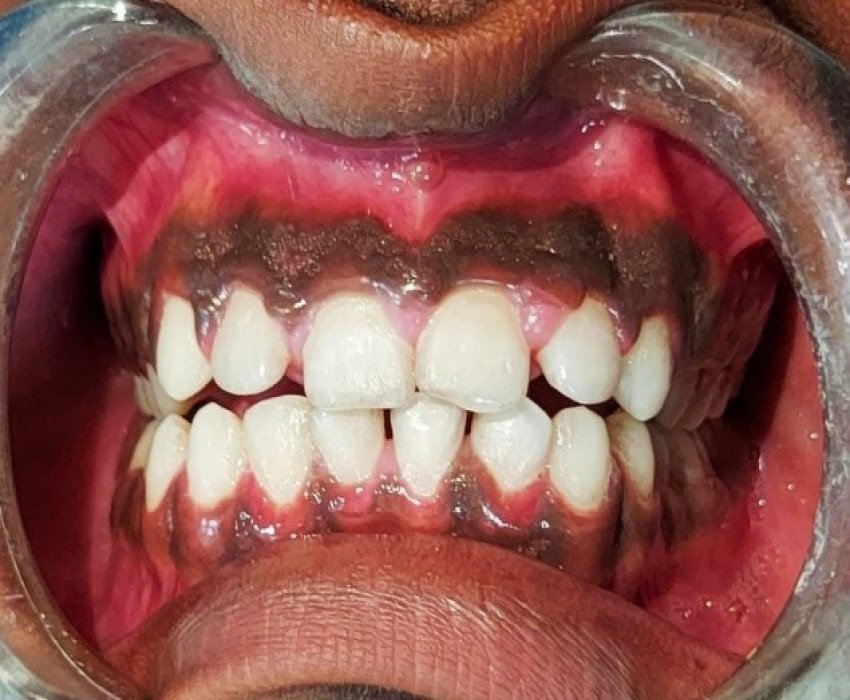

A 15-year-old male patient reported to the Department of Pedodontics, Saraswati dental college, Lucknow, Uttar Pradesh, India with a chief complaint of localized gingival enlargement in the upper anterior teeth region since last 9-10 months.

Idiopathic gingival enlargement with hyperpigmentation

- Gingivectomy, Depigmentation with Laser